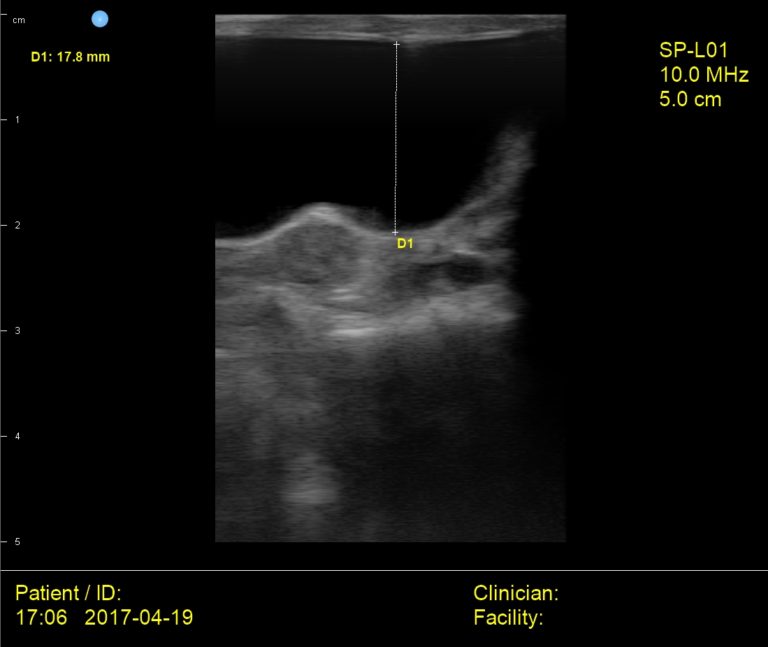

From interson.com

Interson Cat Bladder Ultrasound Image Interson Corporation Cat Bladder Ultrasound The urinary bladder is best visualized if it is full of urine; Therefore, do not let your cat urinate within three to six hours of the ultrasound procedure if possible. Always evaluate the trigone area carefully, particularly as it Ultrasound examination of the kidneys and perinephric space can provide important information on several conditions including chronic renal disease, hydronephrosis and. Cat Bladder Ultrasound.